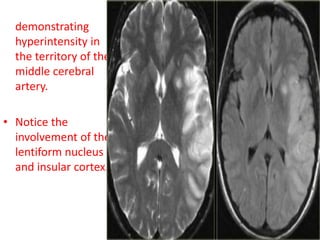

• T2WI and FLAIR

demonstrating

hyperintensity in

the territory of the

middle cerebral

artery.

• Notice the

involvement of the

lentiform nucleus

and insular cortex.